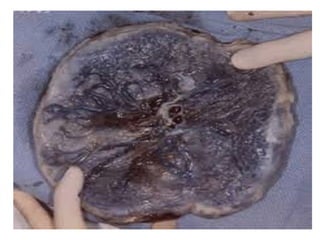

Circumvallate Placenta

It is the variation in the normal shape of the

placenta in which the chorionic plate on the fetal

side is too small. In this condition, the fetal

membranes ‘double back’ on the fetal side

around the edge of the placenta . The condition

result in a decreased supply of nutrients to the

fetus.